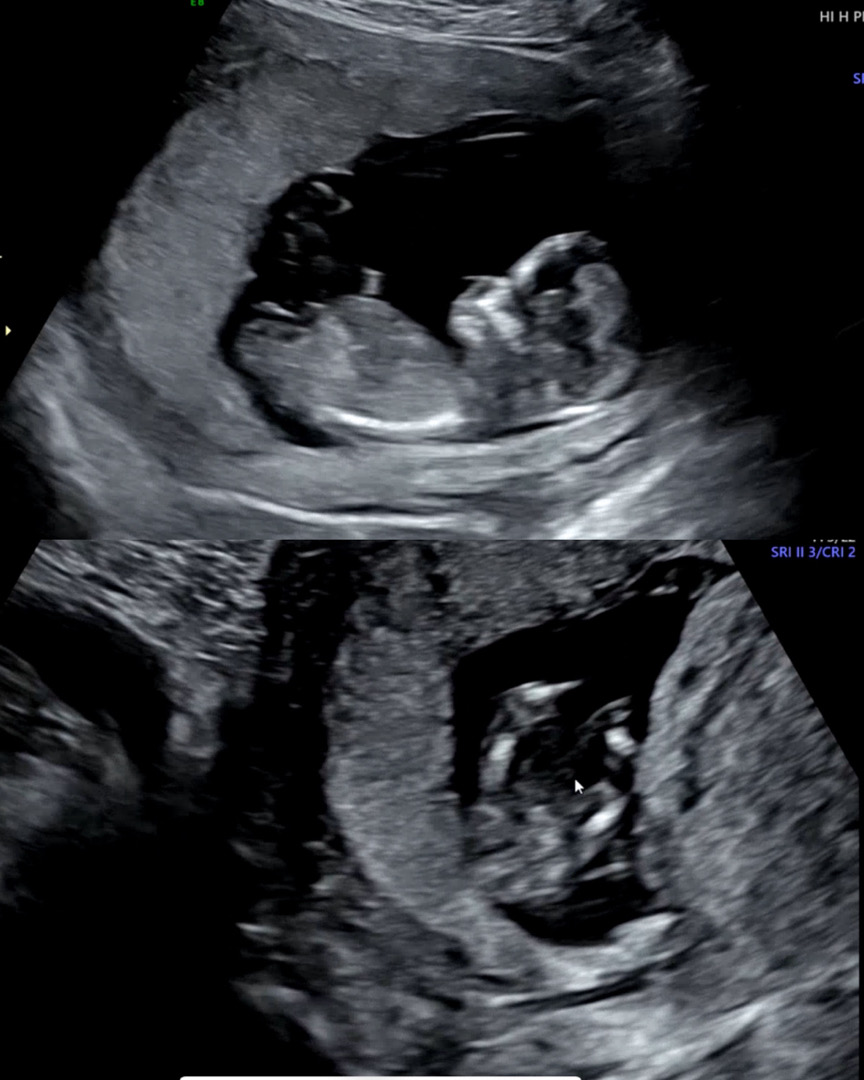

12주3일차 성별 좀 봐주세요!!

병원에서는 아무말 없이 영상만 보여주고 끝이였는데 궁금해서 미치겠습니다ㅠㅠ 12주차 때 성별이 보인다는데 .. 고수님들이 봐주세요! 각도랑 다리사이에 무엇이 보인다는데.. 부탁 드릴게요.